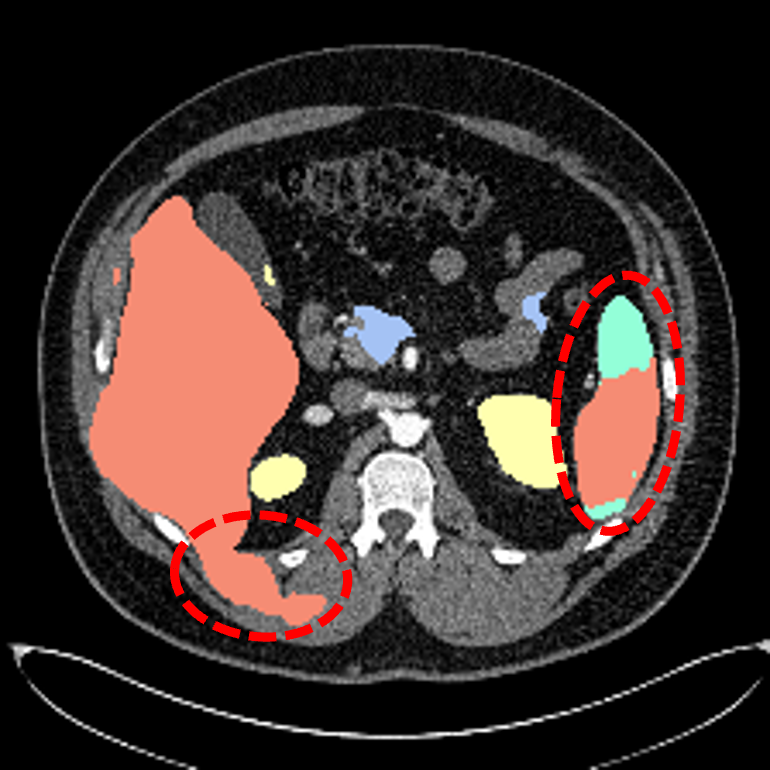

Multi-organ segmentation in CT images: The Synapse multi-organ segmentation dataset [70] contains 30 abdominal CT scans, where 18 (resp. 12) cases are used for training (resp. testing). The goal is to segment 8 abdominal organs. We also conduct evaluations on the AbdomenCT-1K dataset [71] containing more 1000 CT scans from 12 medical centers to benchmark the generalization ability of different methods.

Multi-organ segmentation: For multi-organ segmentation in CT images, Some illustrative results are shown in Fig. 4. Qualitatively, SIKD built on TransUNet [21] accurately segments different organs and preserves their shapes well. The quantitative benchmark on the Synapse multi-organ segmentation dataset is depicted in Tab. 2.

SIKD performs better than the corresponding baseline in terms of both Dice score and HD, implying that SIKD achieves good surface prediction and preserves the shapes better. Specifically, SIKD outperforms the baseline TransUNet by 2.69% Dice score and 8.04 mm HD. Compared with SwinUnet [23], SIKD based on TransUNet achieves an improvement of 1.01% Dice score and 1.89 mm HD. Implementing SIKD with MaxStyle [85] and SAMed [86] also consistently boosts the intra-dataset segmentation performance. The latest 2D D-LKA achieved state-of-the-art (SOTA) performance. Based on this approach, our method improves the Dice score by more than 1%.

We also benchmark the generalization ability of different methods by conducting cross-dataset evaluation on AbdomenCT-1K dataset [71] for the models trained on Synapse multi-organ segmentation dataset [70]. As depicted in Tab. 2, SIKD outperforms all the corresponding baseline models under cross-dataset evaluation. In particular, SIKD built on the baseline of SAUNet [24] improves the baseline model by 11.44% Dice score and 18.48 mm HD. Compared with SAUNet which only incorporates shape information, SIKD achieves 7.17% Dice score and 12.21 mm HD improvement. Building SIKD on SAMed [86] improves the baseline model by 1.6% Dice score and 18.67 mm HD. Based on the SOTA 2D D-LKA method, our approach achieves the best generalization results. This demonstrates that SIKD effectively incorporates the shape-intensity knowledge and generalizes well to images of unseen dataset.